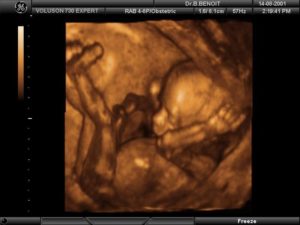

3Д – УЗИ на 16 неделе: проводят ли скрининг?

Современные УЗ – сканеры с расширенными возможностями предоставляют картину плода в 3-D формате, что позволяет специалисту и родителям наблюдать трехмерное изображение малыша. Процедура не требует особой подготовки и длится до 60 мин. Метод отличается точностью данных.

3Д фото плода

Наиболее точную информацию о половых признаках плода можно получить на 3д оборудовании. Трехмерная проекция позволяет врачу-узисту точнее определить половые признаки малыша.